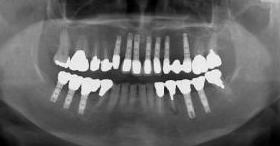

| インプラント治療とは、歯の抜けたところに人工の歯根(インプラント)を植え、あごの骨としっかり固定させた後、その上に人工の歯を装着させたものです。これにより取りはずしの入れ歯の不快感がなくなり、天然歯と同等の力で噛むことが可能となる新しく画期的な歯の治療法です。 |

| 数本のインプラントを植立し、インプラント同士を連結します。入れ歯を固定するバーや止め金が不要となり、口の中がすっきりし、口臭も減ります。 |